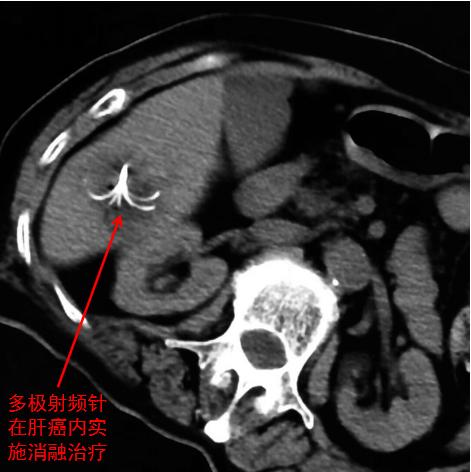

至于介入“消融”,我也曾有文章专门描述,各位也可检索。简要说来,它是在影像设备引导下,通过经皮穿刺,将射频电极或“酒精针”等器械送达病变部位,通过产热或冷冻的物理效应以及无水酒精等的化学作用,对肿瘤组织进行“毁损”。凡是消融效能到达之处,肿瘤均可被彻底灭活(烧掉、冻死、凝固),从而实现“根治”目标,相当于不开刀就把病灶拿掉了!